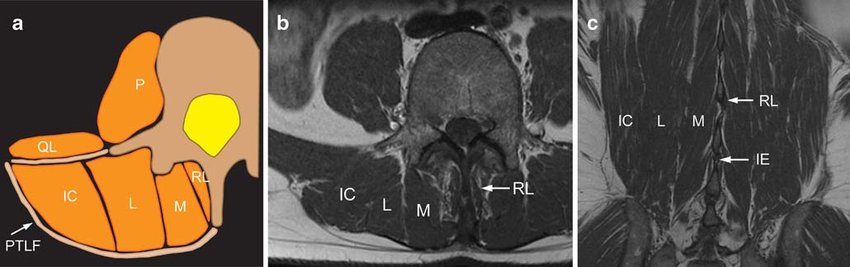

바로 longissimus와 multifidus, iliocostalis, spinalis 입니다. 앞의 3개의 근육은 허리를 펴는 역할을 하기 때문에 Erector spinae 라는 명칭으로 불립니다.

Axial view 에서 보게 되면 Psoas muscle과 Quadratus lumborum 뒤쪽으로 위치하는 허리폄근을 확인할 수 있습니다.